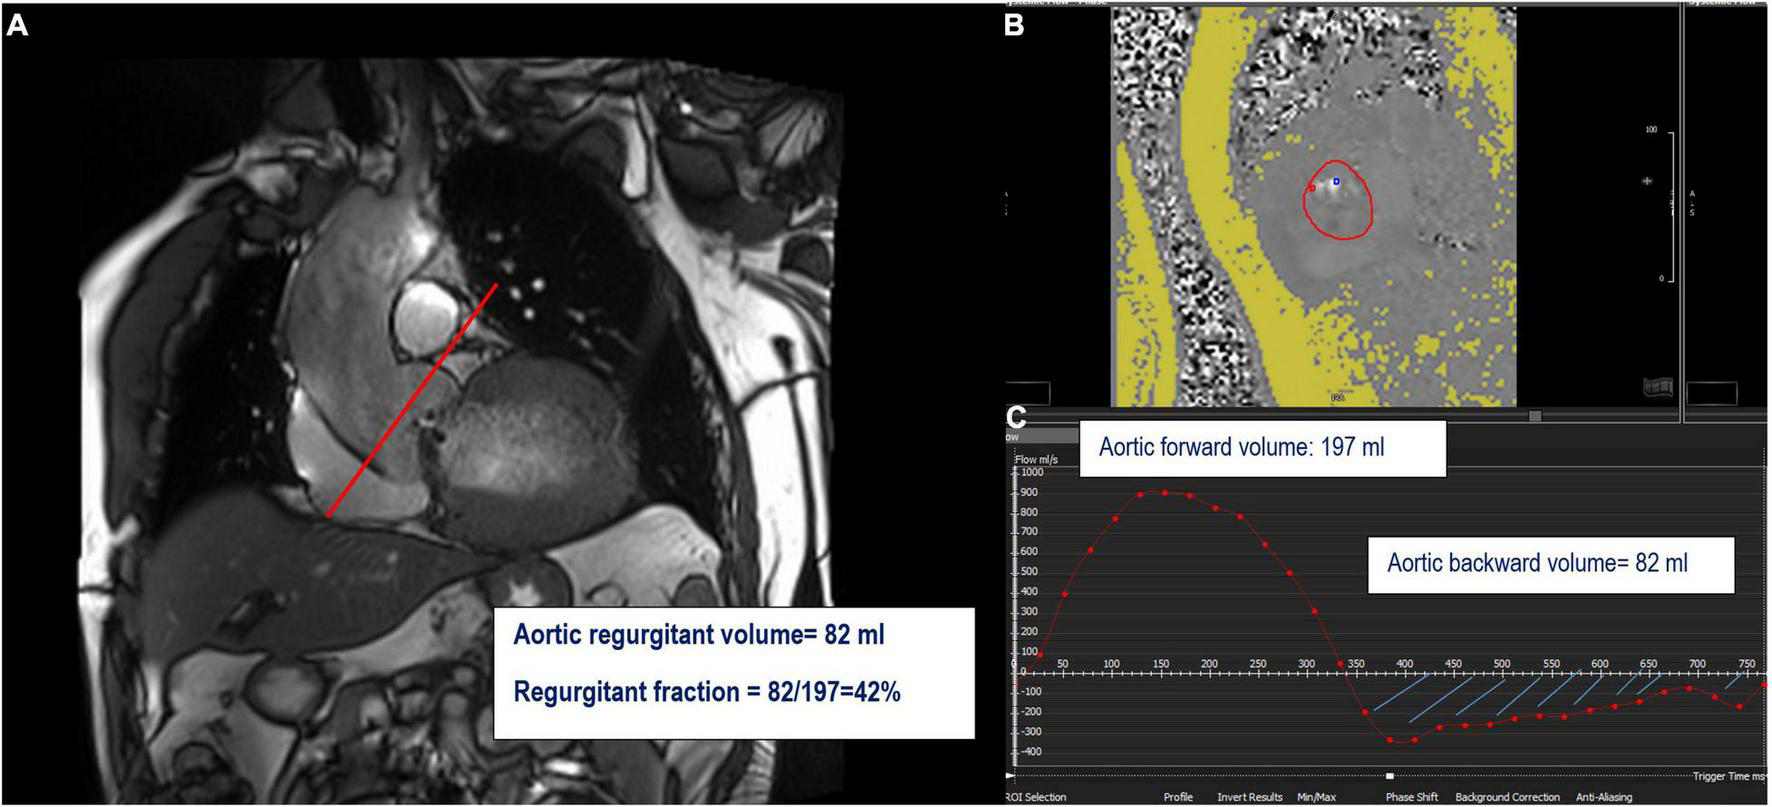

FIGURE 5

Example of the direct quantification of aortic regurgitation by phase-contrast imaging. Perpendicular line (red) above the aortic valve on LVOT view indicating the slice position for phase-contrast velocity mapping (A) generating phase images (B) and flow curves images (C). The aortic regurgitant volume (ARvol) is represented by the area under the diastolic flow curve (blue hatch lines).